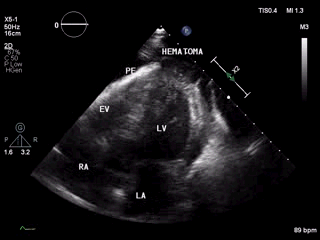

(图1)

(图2)

图1和图2 :术中行心包积液彩超可见:心包腔内见液性暗区:右房顶部  20mm,右室前壁最多时25 mm,右室侧壁旁15 mm。提示:心包积液(中大量)。